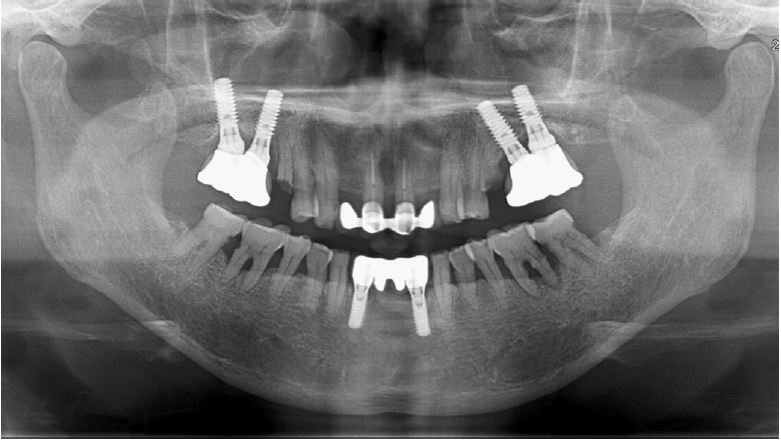

Radiographic examination confirmed root caries and apical lesions in the maxillary left second molar (Fig. 12). It was predicted that the initial stability could be achieved, and extraction and iARP were planned. The patient was instructed to rinse with 0.12% chlorhexidine digluconate solution for 2 minutes for oral disinfection. The left second molar was extracted using luxators and extraction forceps under local anesthesia with 2% lidocaine containing 1:80,000 epinephrine (Fig. 13A, 13B). After debridement of granulation tissues in the apical area and irrigation with a sterile normal saline solution, immediate implant placement (TS III 5.0 × 8.5 mm; OSSTEM) was performed (Fig. 13C). The ISQ value at first surgery was 60. The gap between the implant surface and the extraction socket wall was filled with DBBM and covered with NBCM in a double-layer fashion (Fig. 13D, 13E). The hidden X suture and horizontal mattress suture were placed over NBCM without primary wound closure (Fig. 13F, 13G). Fourteen days after surgery, the patient returned for suture removal and postoperative examination. Healing of the depressed soft tissue above the extraction socket is observed. After four weeks, soft tissue depression continued, but epithelial healing was complete (Fig. 13H, 13I).

Fig. 13.

Case 3: Clinical photographs of the immediate implant placement with alveolar ridge preservation. (A) Initial clinical photograph of the left maxillary second molar, (B) The tooth was extracted without any gingival damage, (C) Immediate implant placement in the left maxillary second molar, (D) Deproteinized bovine bone mineral is placed in the extraction socket and covered with a native bilayer collagen membrane, (E) Extraction socket and covering with native bilayer collagen membranes, (F) Hidden X and horizontal mattress sutures are placed, (G) Panoramic radiograph obtained after implant placement, (H) Yellowish, depressed gingival healing observed at the stitch removal (2 weeks), (I) Depressed gingival healing was observed without inflammation at recall check (4 weeks).